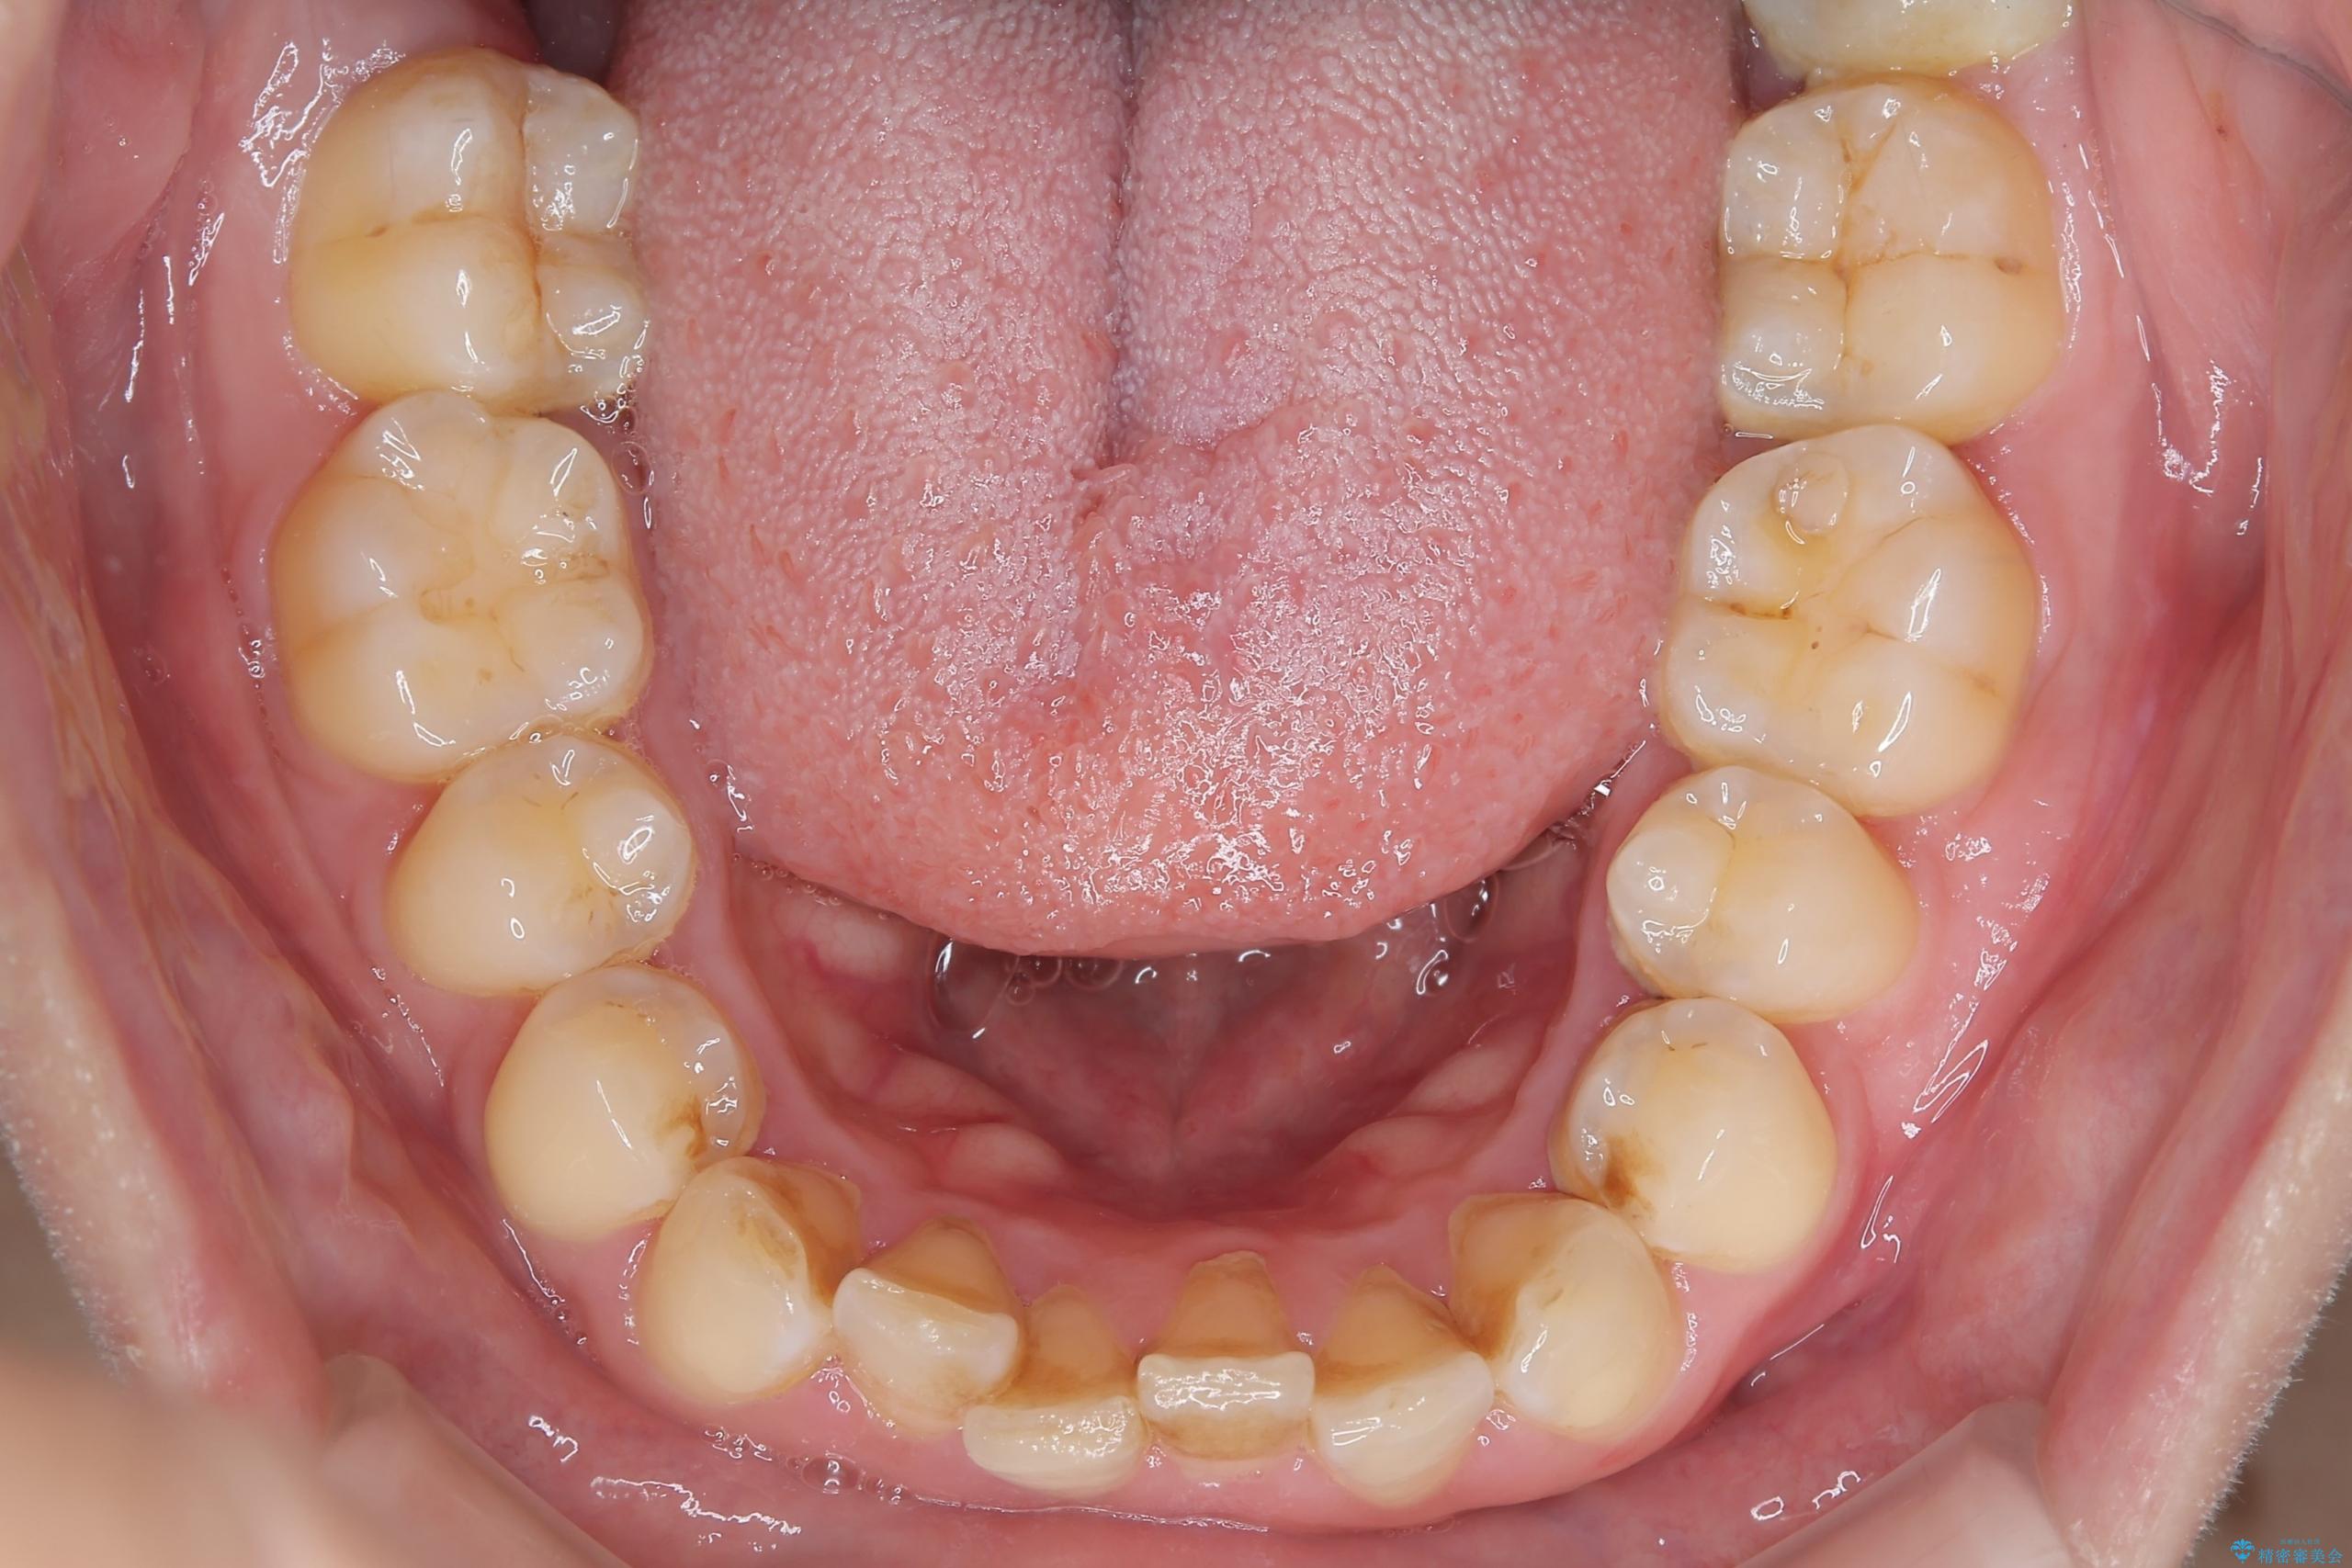

- 下の歯のがたつきを主訴に来院されました。

下の歯のがたつきと右の奥歯の噛みあわせ改善するために治療計画を立てることにしました。

下の前歯のがたつき改善にはIPR(歯と歯の間を削る処置)を行いました。